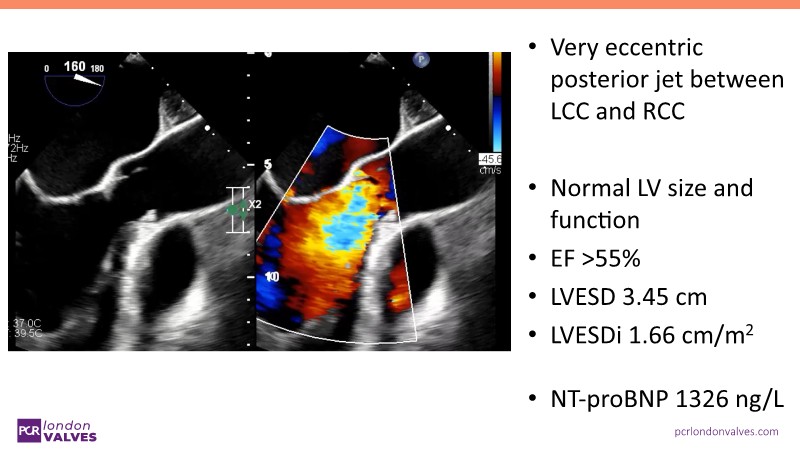

This session examines the evolving treatment landscape for aortic regurgitation (AR) in light of new ESC guidelines and dedicated devices such as the JenaValve Trilogy System. It provides an in-depth look at refined diagnosis, optimized treatment strategies, and presents real-world data and clinical cases that highlight the commercial performance and efficacy of the Trilogy System in Europe.